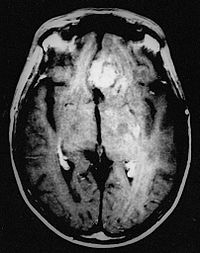

1. Estudios radiológicos:

1. Muestran efecto de masa, así como cambios en el encéfalo adyacente al tumor, como edema. Astrocitomas de alto grado - - - > vasos anómalos que están agujereados y por ello muestran refuerzo con contraste en los estudios de imagen.